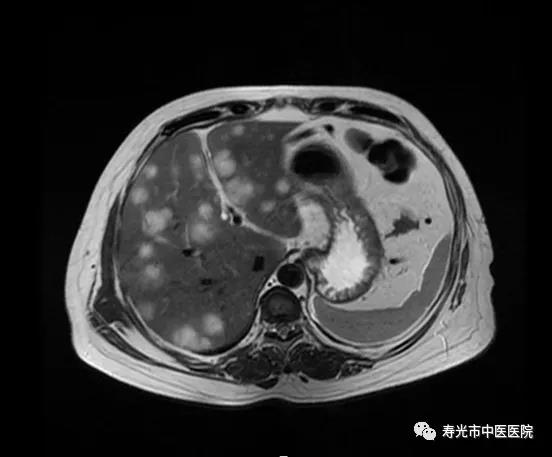

西门子3.0T核磁共振设备为目前国际最先进磁共振机型,代表世界一流水平。其优势集中体现于超大检查孔径,可为患者提供更加舒适的检查环境。全身线圈系统让检查可达到精、广、高、速的效果,丰富而先进的软件为磁共振检查提供众多序列和强大功能,能够更准确、更高效的完成人体各部位磁共振检查,满足各种医学临床需求。李云启说,磁共振扫描主要用于中枢神经系统疾病、各部位血管成像、脊柱及四肢关节病变、头颈部病变、腹盆腔脏器病变等检诊。“尤其对腹部、盆腔脏器病变的检查优势比较大。”

一位患者因为腹痛入院,起初怀疑是阑尾炎,B超发现患者腹内有积液。看到患者入院检查时的血红蛋白极低,医生赶紧安排为患者进行了磁共振检查,检查结果竟是髂动脉瘤破裂,患者腹腔内充满血液。髂动脉瘤突然破裂会危及生命,被称为“不定时炸弹”和“无声的杀手”。患者还未从磁共振仪器上下来,李云启已经通知了医生和患者家属,第一时间对患者进行抢救,将患者从鬼门关拉了回来。

磁共振肝转移瘤成像